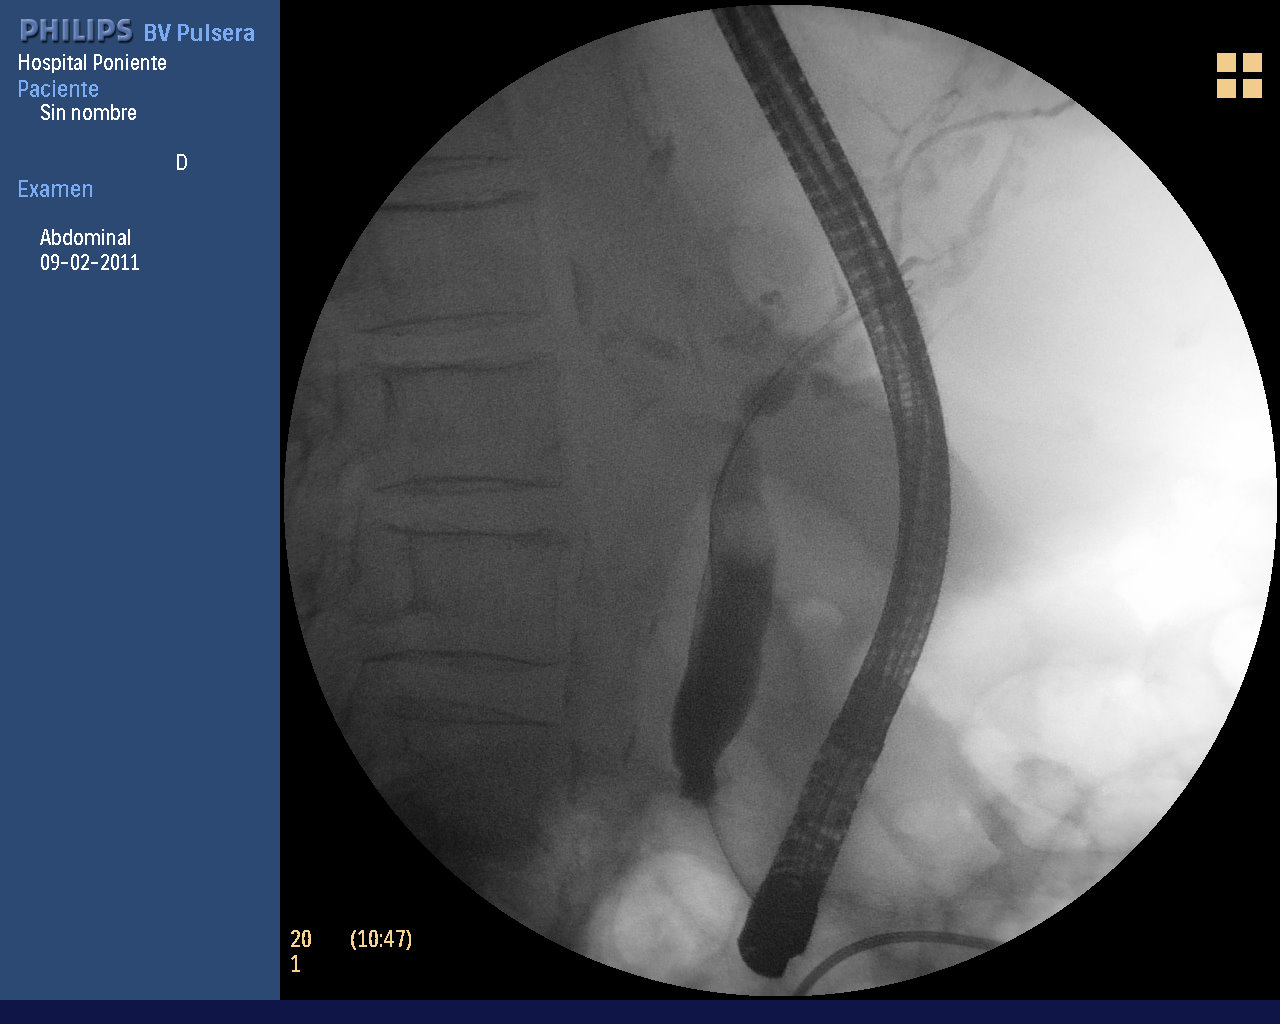

CPRE MORALIZANTE

De vez en cuando apetecen estas CPRE tras esos periodos «tontos» donde aparecen intervenciones complejas y difíciles. Y no digamos si hay complicaciones en las previas. Te dan moral y todos nos contentamos para la próxima.